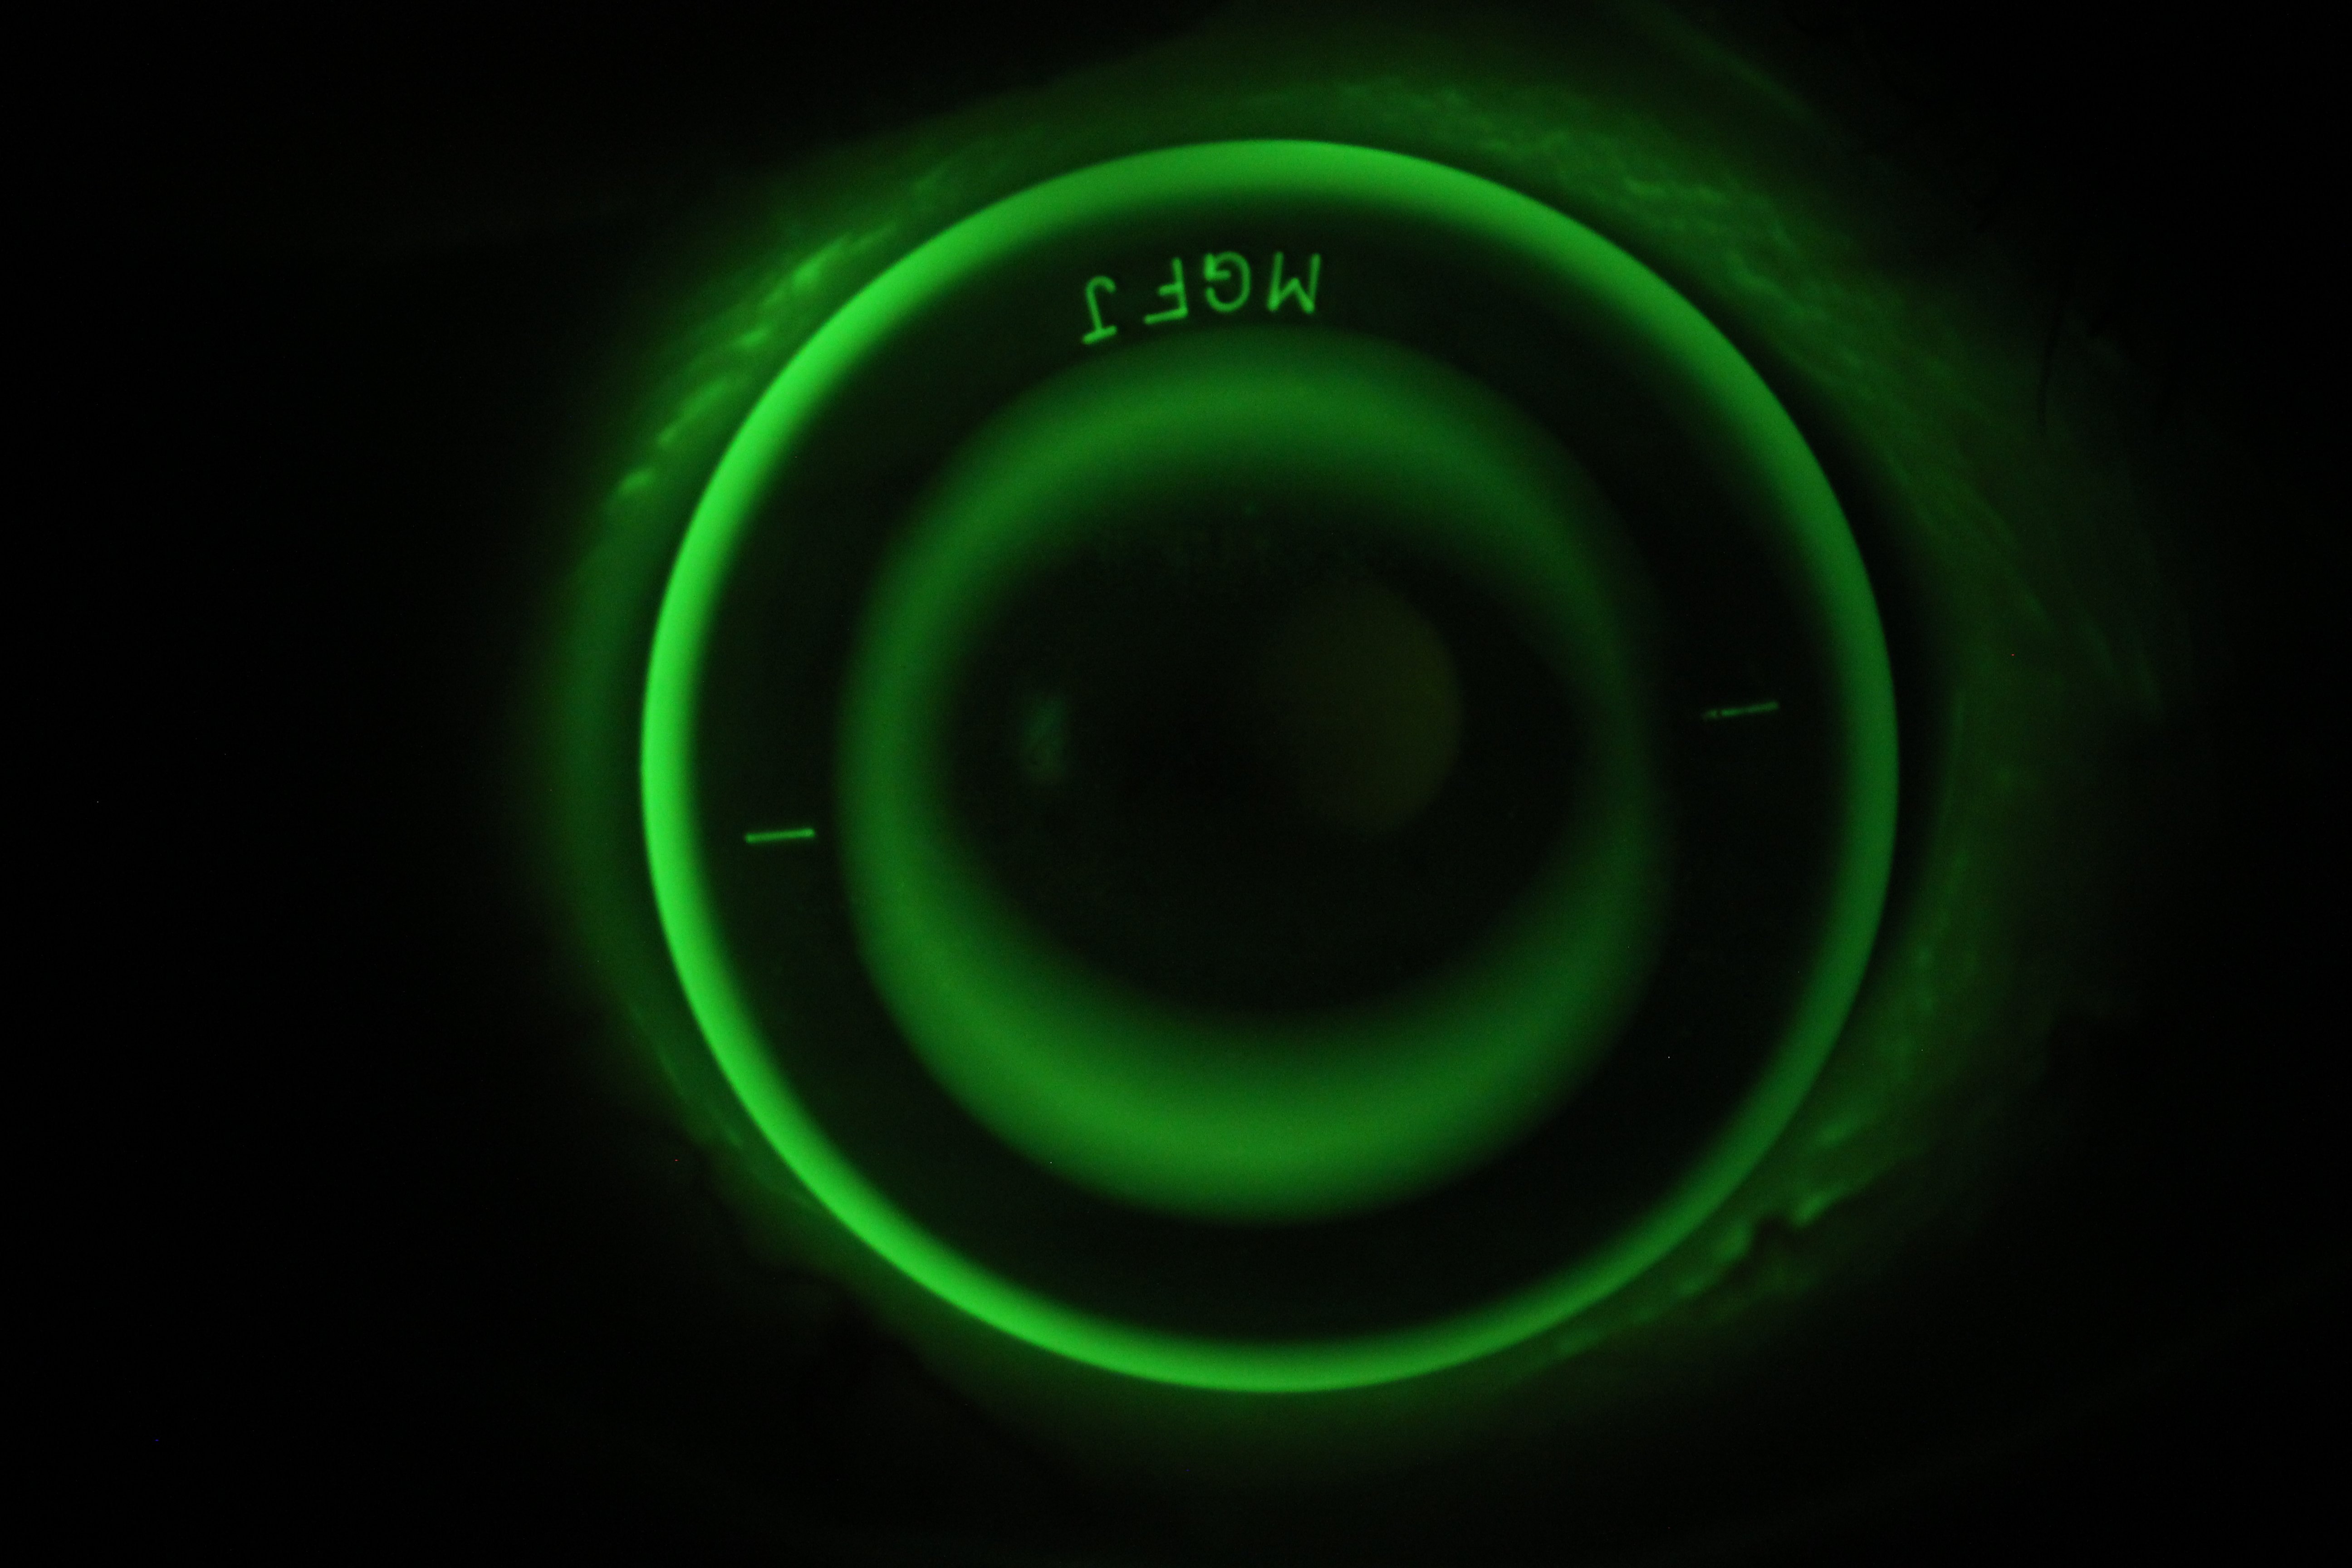

Speciality Contact Lenses – Custom Comfort & Clarity

Innovative Eye Care prescribes custom specialty contact lenses for optimal comfort and clarity. These include scleral lenses, corneal rigid lenses (RGPs) and orthokeratology lenses.

Myopia Control – Protecting Children’s Vision:

Short‑sightedness (myopia) is becoming increasingly common, especially in children. Innovative Eye Care offers orthokeratology (Ortho‑K) lenses, specialised spectacle lenses, MiSight contact lenses and lifestyle guidance to slow progression and protect long‑term vision.